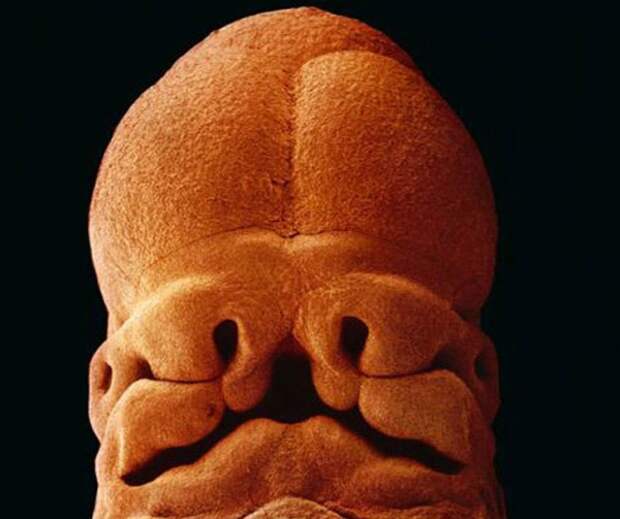

11. 5 недель, длина 9 мм, уже угадывается лицо с отверстиями для рта, ноздрей и глаз.